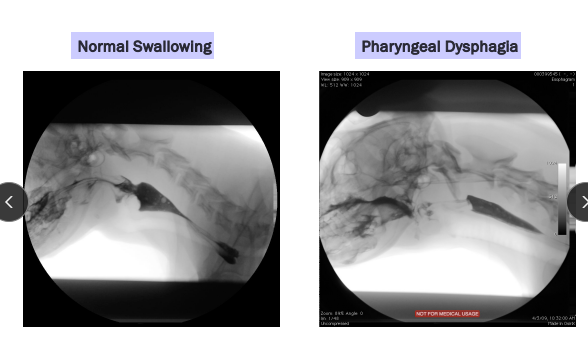

Dysphagia

Et: Dental dz, oropharynx dz

Where:

Only Dysphagia: Oropharynx

With Regerg: Oropharynx + prox upper esophagus

Cs: Difficulty chewing + swallowing

Dt: Oral exam (awake + sedated), imaging, endoscopy

Comp: Aspiration pneumonia, malnutrition, weight loss

Anatomy: history, video, observe eating, oropharyngeal exam (awake + sedated), rads of skull + pharynx + thorax

Fxn: fluoroscopy, endoscopy, neuromuscular evaluation